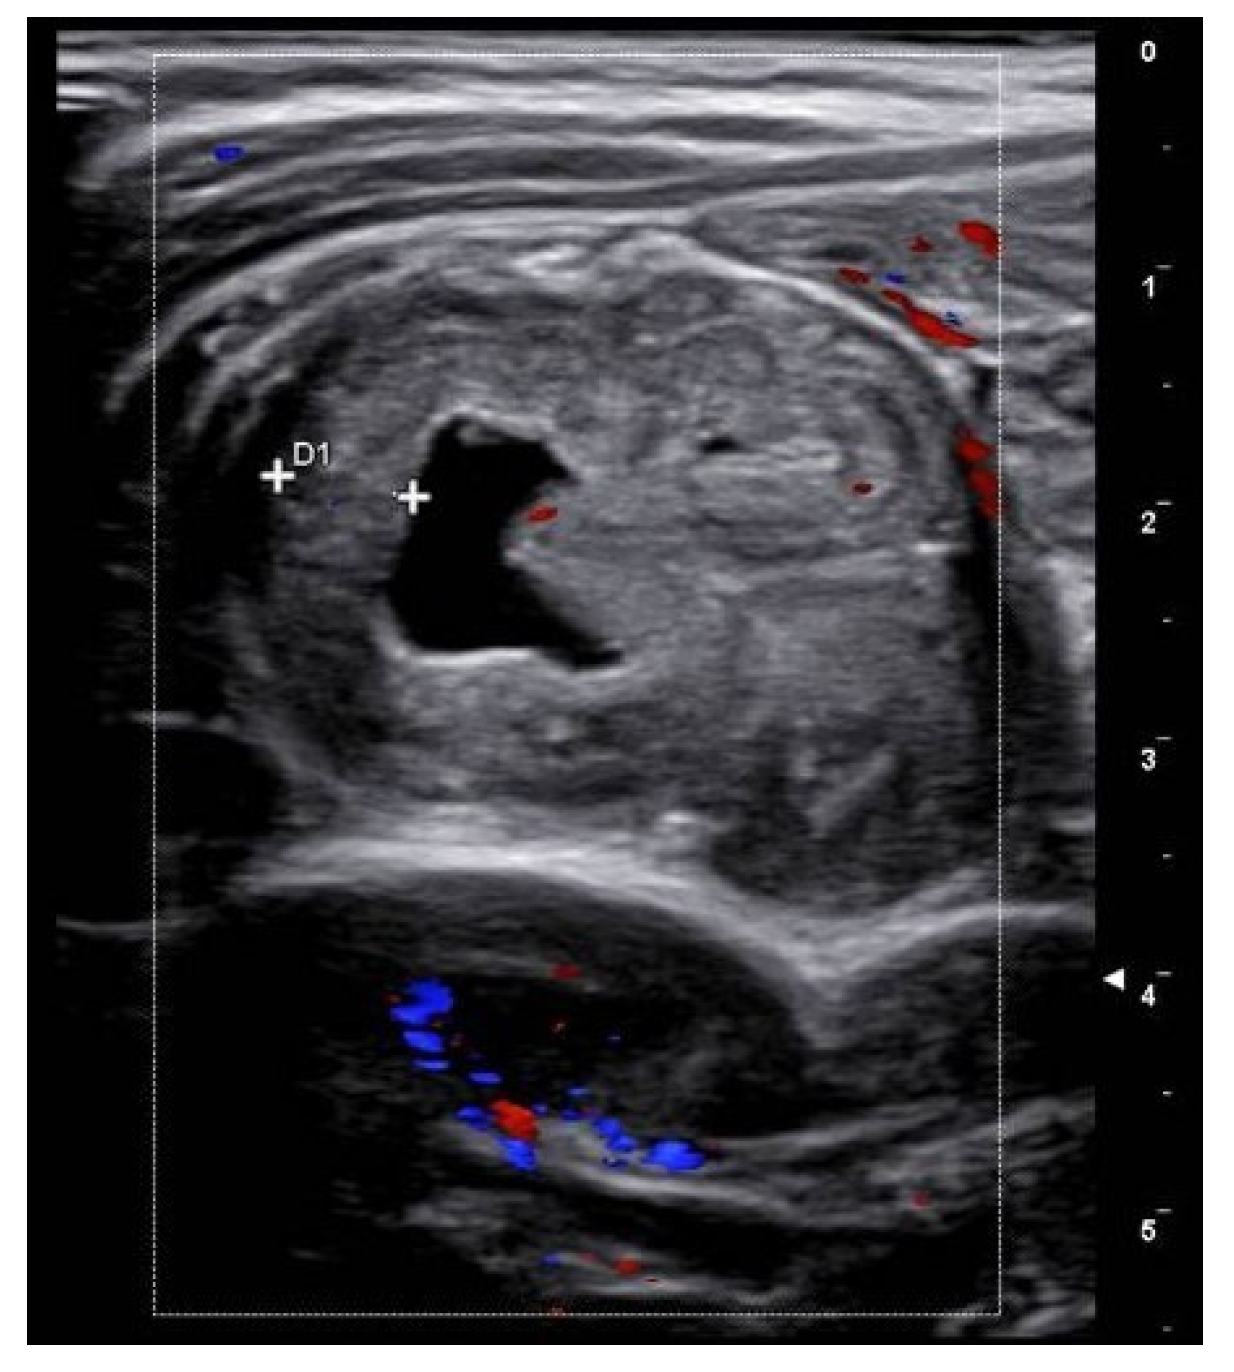

Figure 1.

Case 1—US showing the thickened wall of the suspected Meckel’s diverticulum.